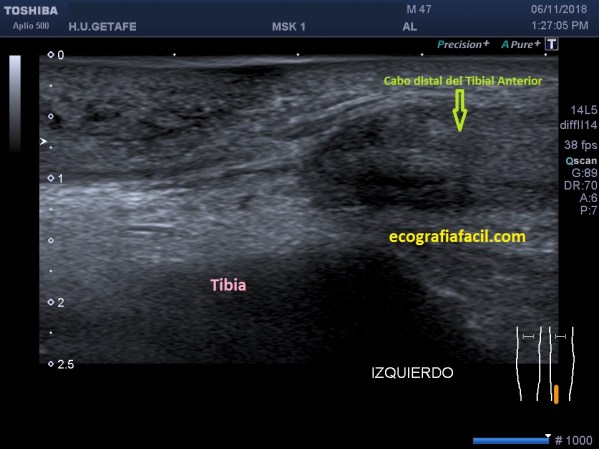

¿Cómo se vive ecográficamente este escenario? Los dos cabos del tendón se separan y se retraen, se vuelven hipoecogénicos, grandes y entre ellos existe un espacio que estará ocupado por derrame, grasa y además un efecto de «perdida de contorno» en la piel.

En las imágenes superiores y como si fuesen fotogramas ves:

- Cabo distal del tibial anterior en corte longitudinal.

- Cabo distal del tibial anterior en corte axial.